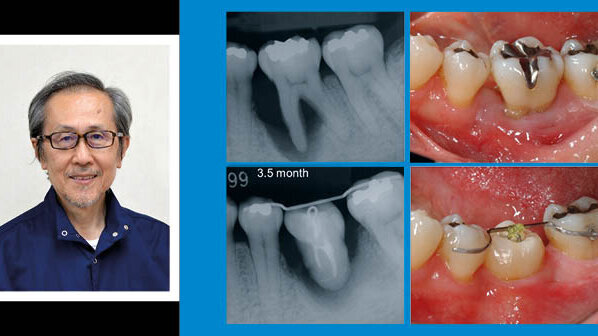

Д-р Мицухиро Тцукибоши е възпитаник на денталния факултет на Университета в Осака. Притежава докторска степен по дентални материали от Университета в Киото през 1980 г., а от 1981 г. ръководи частна практика. Интересите на д-р Тцукибоши в областта на денталната травматология и автотрансплантацията са причината за неговото значително участие в редица клинични проучвания, обучения и научни публикации. Д-р Тцукибоши изнася лекции в цял свят, посветени на денталните травми и автотрансплантацията; автор е на множество статии и два учебника – един за денталните травми (издаден през 1998 г., второ издание през 2012 г.) и един за автотрансплантацията (издаден през 2000 г.). И двата учебника са преведени на няколко езика, включително английски. Д-р Тцукибоши е гост преподавател в университета „Лома Линда“ от 1998 г. Той е бил президент на Международната асоциация по дентална травматология през 2009 и 2010 г.